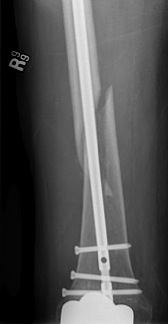

Case 1

Periprosthetic TKR Tibial Fracture 1Periprosthetic TKR Tibial Fracture 2Periprosthetic TKR Tibial Fracture 3Periprosthetic TKR Tibial Fracture 4

TKR Periprosthetic Fracture APTKR Periprosthetic Fracture LateralTKR Periprosthetic Fracture Revision APTKR Periprosthetic Fracture Revision Lateral